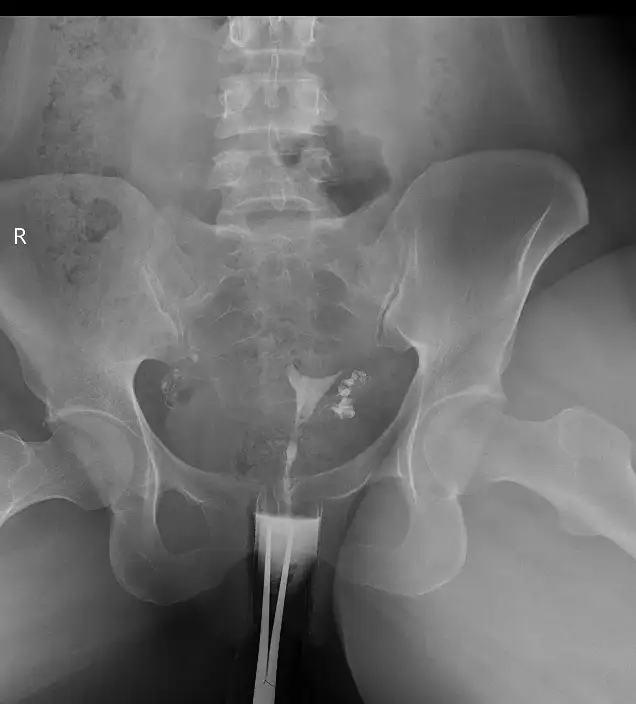

merhaba bende rahim filmi çekildim nisan ayında son adetimi de haziranda gördüm şimdi hamileyim şükür .hatta hamile kaldığım ay çatlatma iğnesi yapacaktım ama bulamamıştım .ama benim her iki tüp açıktı .kız kardeşim de tek tüp açıktı malesef onun nırmal yolla gebelik oluşmadı 3. aşılama sonucunda ikizleri oldu çok şükür rabbim isteyen herkese nasip etsinMerhaba bugün hsg çektirdim ama bir tüpüm tıkalıydı ve açılmadı diğer tüp den ilaç geçti bu şekilde tek tüpü kapalı olduğu halde rahim filmi çektirdikten sonra hamile olan varmı aranızda

Bana korun falan demedi hiç bu ayı değerlendir dedi açıldıysa dedi gebelik olur dedi ama açıldı falan demedi yani kafam takıldı baya acılmışmıdır bu ilacı üç kez verdi çok acılı geçti baya ben yapcak olanları korkutmak istemiyorum ama hala sancım var belki bünyeden bünyeye değişebilirMerhaba bende şeyi merak ediyorum rahim filmi sonrası korunmak gerekiyormu yoksa direk o ay baslanıyormu

Maşallah canım bazılarında evet hiç tıkanıklık olmuyor bana da sadece bir tarafta geçiş olmadı dedi beni detaylı aydınlatmalar sonucumu alıp kadın doğum doktoruma göstericemBen 2020 de devlet has de anestezi almadan ama çok acı olmadan çekildim. O ay korjnun dediler korunduk. Diğer ay hamile kaldım.ama bana tıkanıklık yok demişlerdi.

Maşallah peki sana tıkalı falan dedi mi canımMerhaba bende o ay Hamile kalmıştımsadece 3 gün antibiyotik süresince ilişki yasaktı